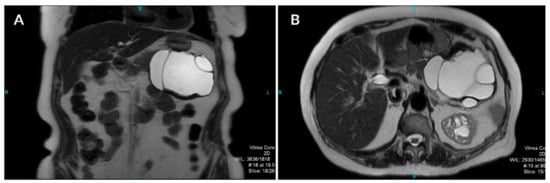

Pancreatic Hydatid Cyst Misdiagnosed as Mucinous Cystadenoma: CT and MRI Findings

2. Case Report